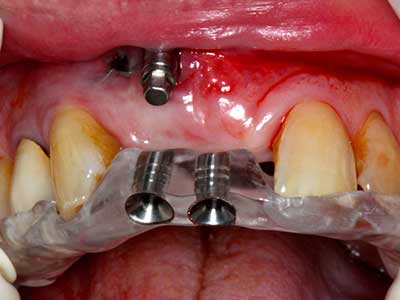

Фиг. 13: Подходяща иригация с остатъчна 4 mm дебелина на костта е важна за този 52-годишен пациент по време на разделянето на костта.

Фиг. 14: Поставяне на RSX имапланта (Bego Implant Systems, Bremen).

Фиг. 16: Интраоралните условия също са стабилни с поставените импланти в кератизираната гингива.